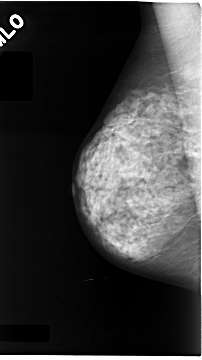

C_0052_1.RIGHT_MLO

LEFT_MLO LINES 4672 PIXELS_PER_LINE 2832 BITS_PER_PIXEL 12 RESOLUTION 50 NON_OVERLAY

RIGHT_MLO LINES 4680 PIXELS_PER_LINE 2616 BITS_PER_PIXEL 12 RESOLUTION 50 NON_OVERLAY